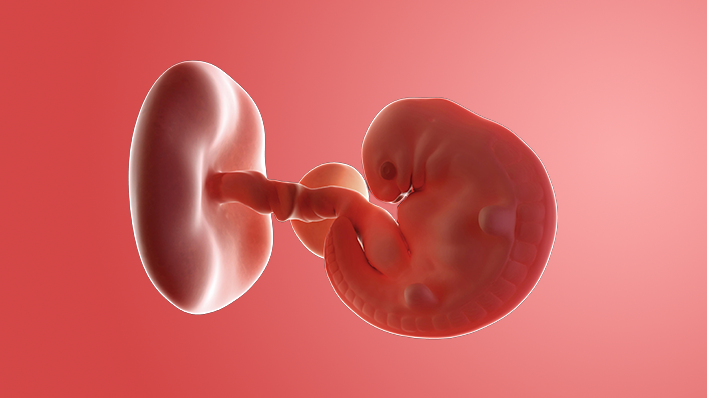

Your baby, or embryo, is about 2mm long (about the size of a poppy seed) and growing rapidly in your womb.

It's protected by an amniotic sac, which is filled with cushioning fluid, and attached to a tiny yolk sac that provides all the nourishment it needs.

The outer layer will later develop into the placenta and provide your baby with oxygen and nutrients.